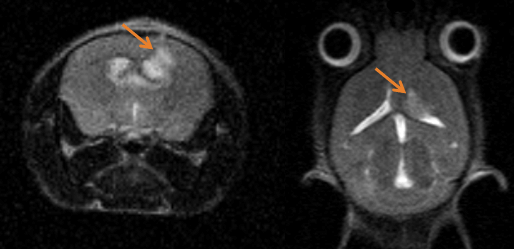

Epilepsy in the rat brain: T2- weighted images of a rat brain 48 hours after induction of epilepsy.

Epilepsy in the rat brain: T2- weighted images of a rat brain 48 hours after induction of epilepsy. Image Credit: Scintica Instrumentation Inc

T2- weighted images of a rat brain 48 hours after induction of epilepsy.

T2- weighted images of a rat brain 48 hours after induction of epilepsy. Image Credit: Scintica Instrumentation Inc